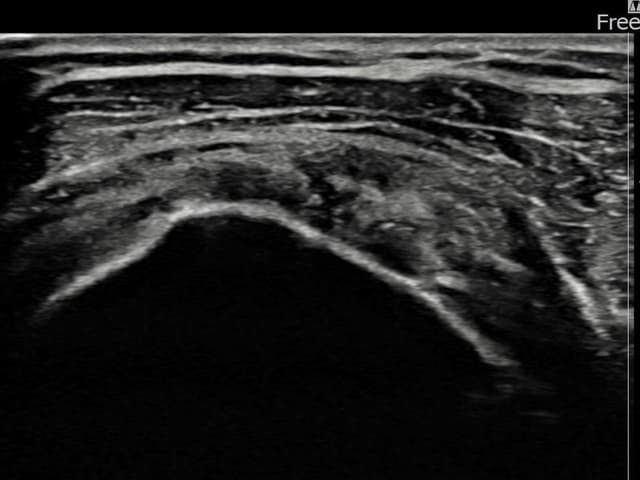

[촬영시기:22.10.06~22.11.14]

[어깨인대 축소봉합술] 좌측 어깨 극상근건 광범위 파열로 수개월간 일상생활이 어렵던 중 내원하셨습니다.